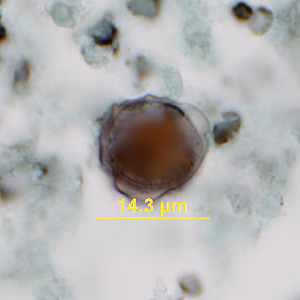

A 26-year-old female presented at a local hospital with severe pain and bloody discharge from the ear. The symptoms started while on a returning flight from vacation in Central America. The patient explained that while on vacation she visited a local physician to have a fly removed from her ear canal.